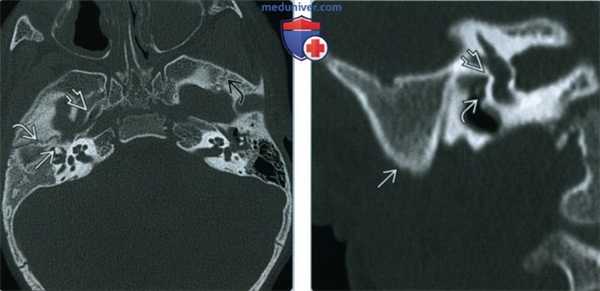

(Слева) При аксиальной КТ в костном окне у мальчика 23 месяцев с ГФМ определяется гипоплазия и снижение пневматизации полости среднего уха справа, дисморфия слуховых косточек. Евстахиева труба справа аномально расширена. Правый клиновидно-чешуйчатый шов В развернут кнаружи по сравнению с левым.

(Справа) На реформатированной корональной КТ в костном окне у этого же пациента отсутствует пневматизация сосцевидного отростка, определяется атрезия овального окна и аномальный ход тимпанического сегмента ЧН VII, проходящего через промонториум.

2. КТ при гемифациальной микросомии:

• Мыщелок уменьшен в размерах или отсутствует

• Суставная ямка сформирована пропорционально размерам и функции мыщелка

• Ипсилатеральная ветвь и тело нижней челюсти недоразвиты:

о Ветвь и тело нижней челюсти сформированы пропорционально мыщелку

• Окклюзионная плоскость приподнята на пораженной стороне

• Иногда обнаруживается расщелина неба

• Скуловая кость и скуловая дуга уменьшены в размерах

• Гипоплазия сосцевидного отростка

• Дистопия глазницы: глазница смещена кнаружи и книзу

• Дефекты среднего и наружного уха